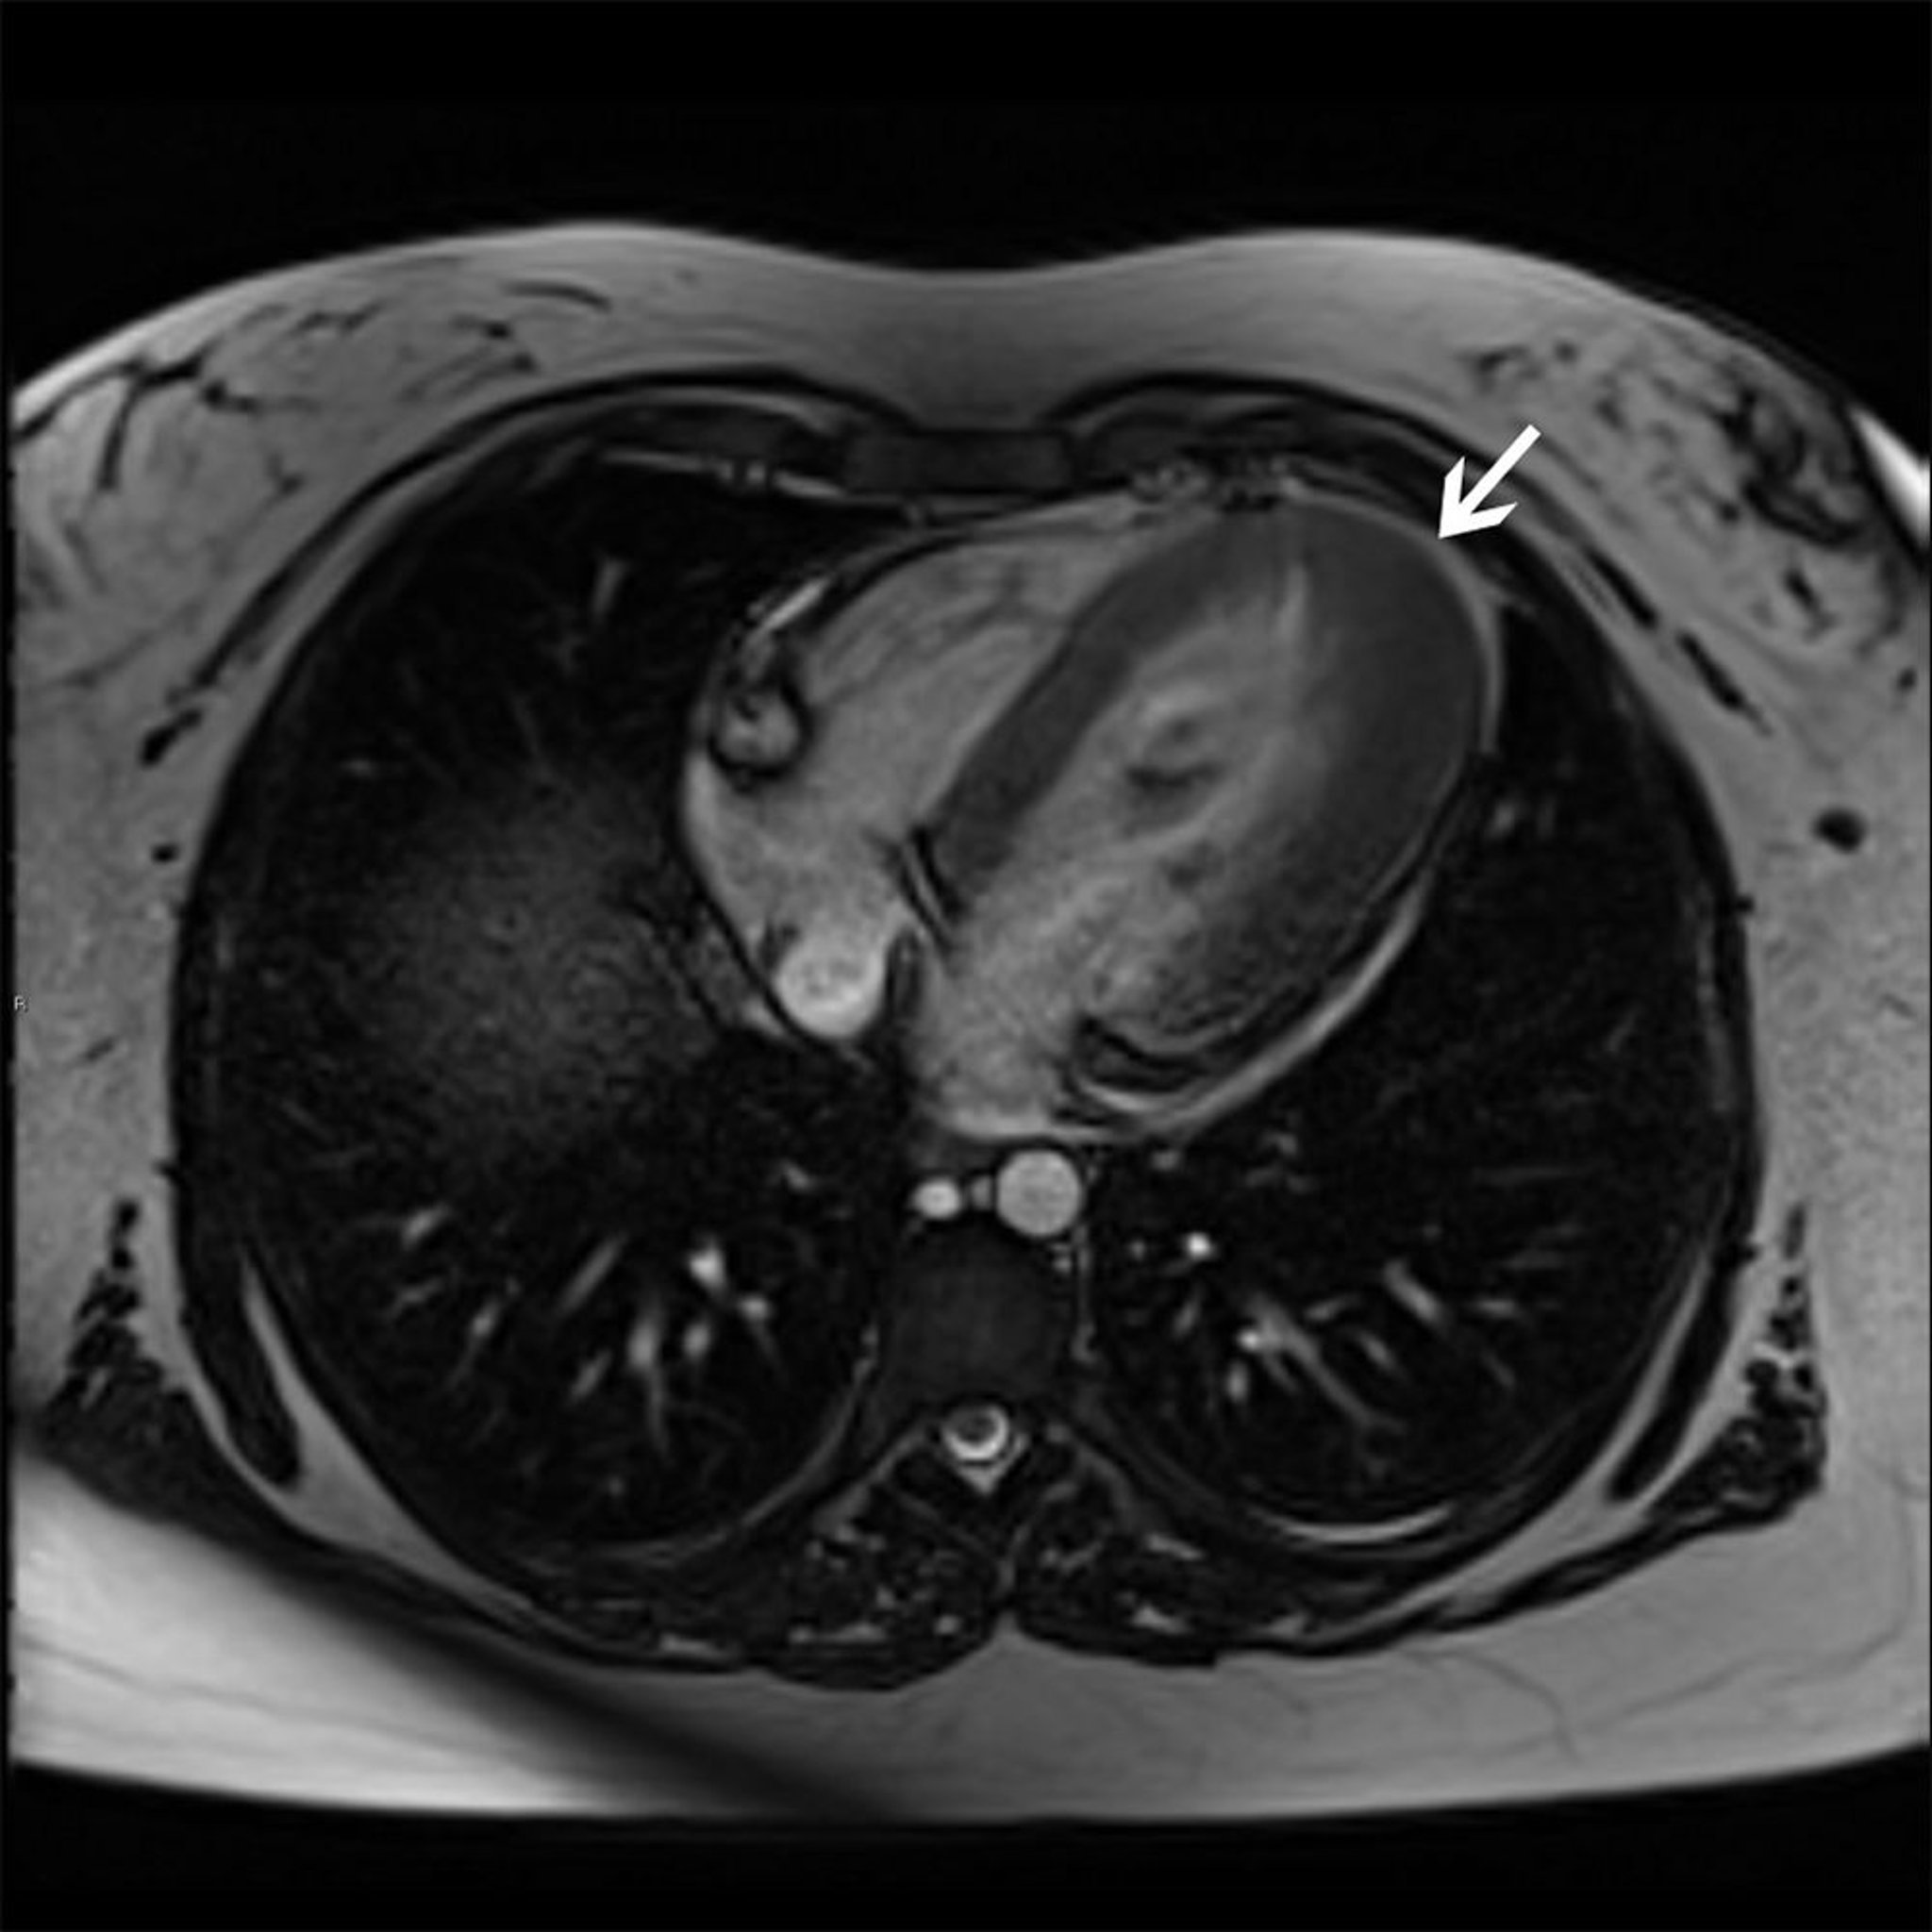

肥大型心筋症(心尖部型)

この心臓MRI画像には,心尖部肥大型の肥大型心筋症が示されている(矢印)。

© 2017 Elliot K.Fishman, MD.